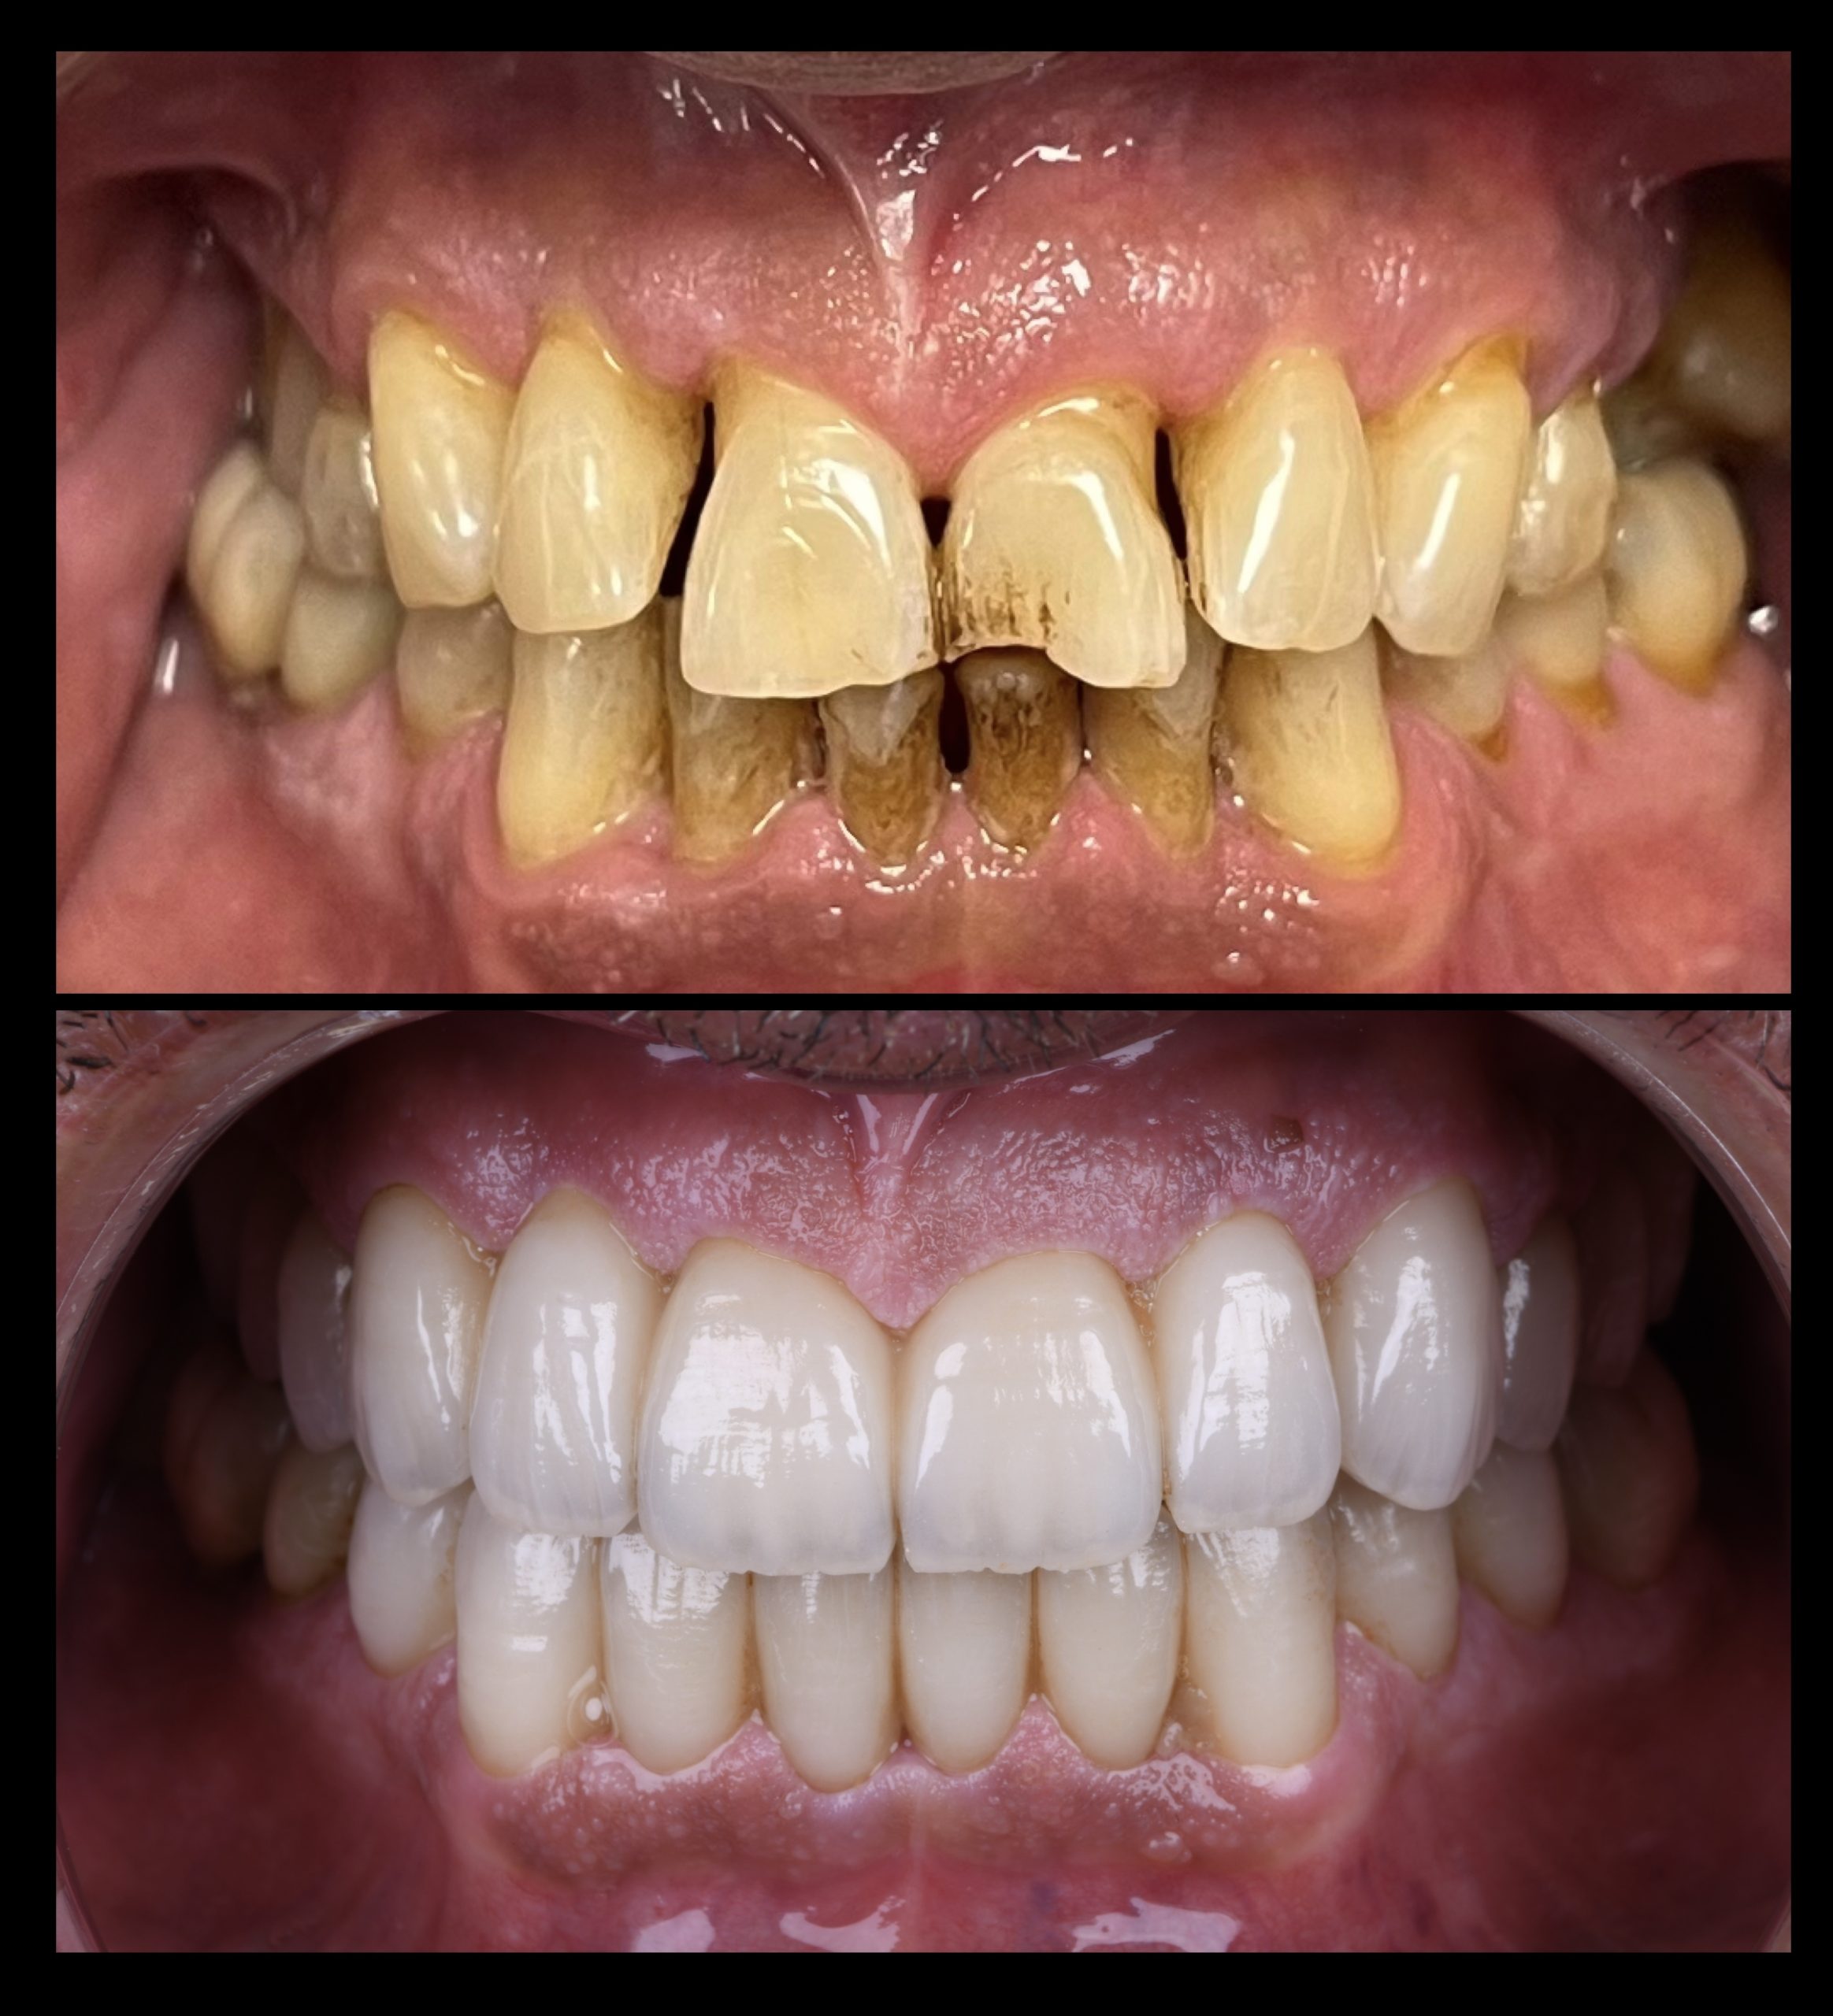

Protetika

Protetika je grana stomatologije koja se bavi rekonstrukcijom i nadoknadom zubnih tkiva usled nedostatka ili gubitka zuba, ili dela zuba

Estetska Stomatologija

Savremena estetska stomatologija koristi materijale vrhunskog kvaliteta koji verno imitiraju prirodan izgled zuba